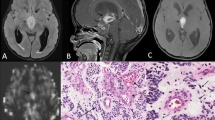

The NAA/Cr values in the PA group were significantly higher than those in the hemangioblastoma group (Table 2 and Fig. 2). There were no statistically significant differences between the hemangioblastoma and PA groups in the remaining metabolite ratios.

Comparison of NAA/Cr, Cho/Cr, and Lac-Lip/Cr ratios on short-TE single-voxel MR spectroscopy in hemangioblastomas and pilocytic astrocytomas. a, c Axial contrast-enhanced T1-weighted imaging was used for positioning of the regions of interest in the tumor. a, b The solid homogenous enhancing hemangioblastoma in the left cerebellar hemisphere had a NAA peak. c, d Cystic solid pilocytic astrocytomas located in the cerebellar vermis also had an NAA peak (d), but the NAA/Cr ratio in this tumor was higher than that found in the hemangioblastomas (b)

Proton MR spectroscopy can be used to acquire information on the metabolism of brain tissue [17, 24]. NAA is generally thought to present in high concentrations in the normal neurons and axons, and its presence may be an indirect marker for tumor composition according to the density of residual neuronal cells within a tumor. Cho has been recognized as a main component of membranes and could reflect the rate of cellular membrane turnover and cellular density. Lactate is an end product of the anaerobic glycolytic cycle whose concentrations within a tumor may indicate the tumor necrosis [25, 17]. The presence of lipids has been recognized to originate from mobile lipid molecules as a result of tissue necrosis and degradation [26]. To our knowledge, there are no reports in the literature on the application of MRS to differentiate hemangioblastomas from pilocytic astrocytomas. In this study, we found that only NAA/Cr ratios in hemangioblastomas were significantly lower than those in PAs among all metabolite ratios analyzed. The NAA/Cr ratio was decreased in both tumor types but much lower in hemangioblastomas, which might be due to the different histogenesis and histological behavior between the two tumor types. PAs have been recognized to rise through the neural axis with infiltrative nature, whereas hemangioblastomas are mainly composed of stromal cells of incompletely differentiated, non-neuronal, and yet neuroectodermal nature [27]. Furthermore, hemangioblastomas are usually well circumscribed and rarely infiltrate adjacent brain tissues [21]. Consistently, this study showed that hemangioblastomas have no neuronal cells or low attenuation of residual neuronal cells with the lesions compared with pilocytic astrocytomas. In particular, NAA was observed only in one case of hemangioblastomas in our study, a phenomenon consistent with an MRS study of a patient of hemangioblastomas reported by Isobe et al. [28]. Although necrosis is seldom found in PAs and hemangioblastomas [17], we found Lac-Lip/Cr ratios increased in both tumor types irrespective of no statistically significant difference between them. The presence of Lac-Lip in PAs without necrosis may be explained by mitochondrial dysfunction [17], while in hemangioblastomas, it may be attributed to lip droplets contained in stromal cells [21].